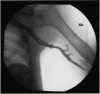

Primary lymphedema tarda is considered to be a congenital disease with delayed manifestations. We report a case of isolated lymphedema of the left upper extremity in an 88-year-old African-American male. The diagnosis of lymphedema was confirmed by lymphoscintigraphy, and appropriate diagnostic studies were done to rule out other known causes of lymphedema. Lymphoscintigraphic findings were consistent with idiopathic primary lymphedema. During the course of investigations, the patient was found to have adenocarcinoma in situ of the sigmoid colon with no evidence of metastatic spread. Based on the available data, we were unable to establish a causative relationship between colonic carcinoma and lymphedema in our patient. Therefore, this case can best be described as a case of Idiopathic primary lymphedema tarda. We emphasize the use of histopathologic examination in the diagnostic algorithm to rule out underlying malignant process only in patients with radionuclide findings suggestive of secondary lymphedema with no obvious etiology.